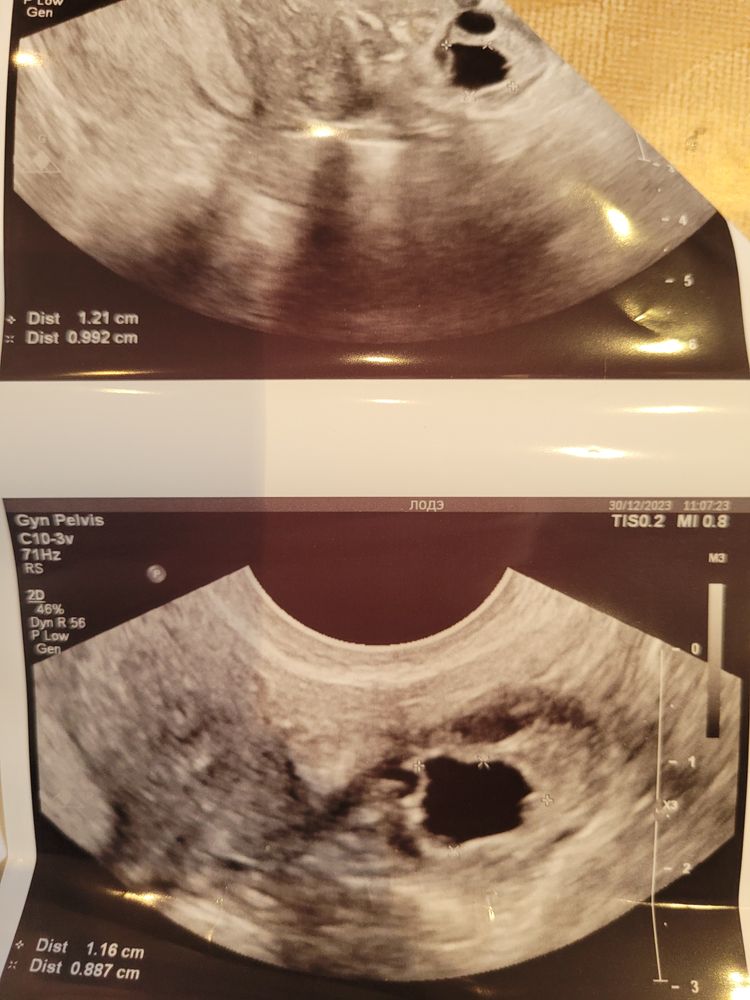

Женечка , я уже в этом месяце 4 раза была. Сначала был фолликул 17 мм, потом он стал 25 мм. Думала фоллик перерос и будет киста. Очень этого не хотелось. Боюсь испортить следующий цикл. Потом пошла проверить, сказали жт 21 мм. На следующий день очень сильно болел живот, пошла ещё раз. Нашли только этот "фолликул" 12.5 мм. Такая интересная история.

Olgita Kashuba, ну по крайней мере у меня на узи так ЖТ выглядит) а фолликул просто кругленький)

Женечка , узисты не могут сказать жт ли это или фолликул. Но обычно жт серое такое на узи. А это черного цвета. Может это сдувшийся фолликул.

Olgita Kashuba, жт может быть смешанной эхогенности (серым неоднородным) и анэхогенным (чёрным) . Смешанной эхогенности- более качественное. Но и то и другое норма

Арина, но почему оно было один день 21 мм, а на другой день уже 12 мм. Сдала на прогестерон сегодня утром, вот и посмотрим.

Юлия, я тут со своим врачом поругалась. Была на одном узи, нашли жт, кровоток. Болел сильно живот, решила перепроверить. Другой врач сказал мне, что это фолликул и у него нету кровотока. Но мой доктор утверждает, что это жт. Но я чувствую, что этот цикл ановуляторный.